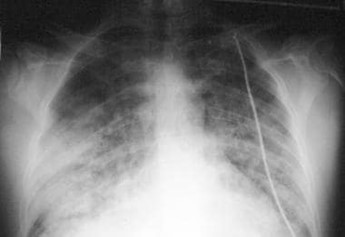

- When available, chest radiography shows patchy bilateral alveolar opacities; nevertheless, localised abnormalities, primarily in the right middle lobe, are possible in early HAPE.

Chest Radiograph in HAPE

A chest X-ray displays signs of bilateral congested lungs. He is immediately shifted to a Srinagar hospital which is at a much lower location where he receives oxygen inhalation and a Chest CT scan is done followed by 2 days in hospital treatment. He made a full recovery and was discharged with a diagnosis of High Altitude Pulmonary Edema and given specific advice to prevent it in future.